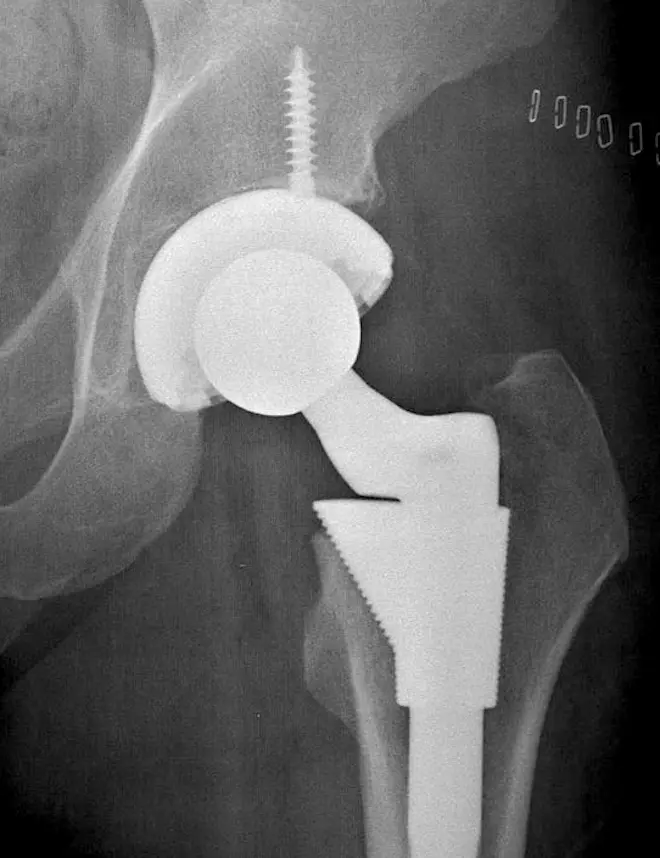

De fait, comme l’observe Le Parisien, de multiples études sur la dispersion de particules métalliques dans le sang des porteurs de prothèse totales de hanche (PTH), liés au frottement de la tête fémorale dans le cotyle (voir ci-contre) ont été publiées depuis le début des années 2000.

Une prothèse de hanche se compose de trois parties. La tige fémorale, qui s'insère dans le fémur ; le cotyle, qui se fixe sur le bassin ; la tête fémorale, enfin, fait la jonction entre les deux premiers éléments. L’ensemble tête fémorale / cotyle constitue le couple de frottement.